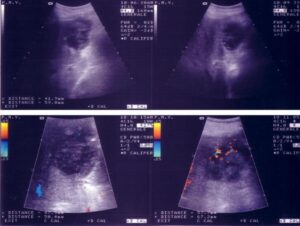

Calcoli alla colecisti, un problema diffuso. A Termini Imerese (PA) la soluzione chirurgica è senza cicatrici Presso l’Ospedale Salvatore Cimino,...

Presso l’Ospedale San Giovanni Bosco di Torino, il Dr. Leandro Moro, dirigente medico del reparto di Chirurgia Generale, centro d’eccellenza...

Presso l’Azienda Ospedaliera-Universitaria di Udine, il reparto di Chirurgia Generale diretto dal Dott. Roberto Petri, centro d’eccellenza per il Friuli...